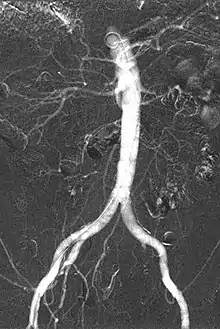

Carbon dioxide angiography is a diagnostic radiographic technique in which a carbon dioxide (CO2) based contrast medium is used - unlike traditional angiography where the contrast medium normally used is iodine based – to see and study the body vessels. Since CO2 is a non-radio-opaque contrast medium, angiographic procedures need to be performed in subtractive angiography (DSA).

Carbon dioxide is a negative contrast medium and it has a low radiopacity (while iodinated contrast media are defined as positive contrast media due to their high radiopacity). Contrast is caused by the different X-ray absorption coefficients between the tissue and the contrast agent. In the vascular imaging results produced using CO2, vessels look brighter rather than the surrounding tissues, because the contrast medium absorbs less X-ray radiations rather an iodine-based contrast medium, where the vessel are displayed in black.

The CO2 does not mix with blood. At atmospheric pressure CO2 is in gaseous form and, when it comes out from the catheter, it forms a train of bubbles which displaces blood, causing a transient ischemia, in relation to the bloodstream (systolic pressure). When added together by DSA “stacking” software,[4] the result is a composite diagnostic image of the frames.